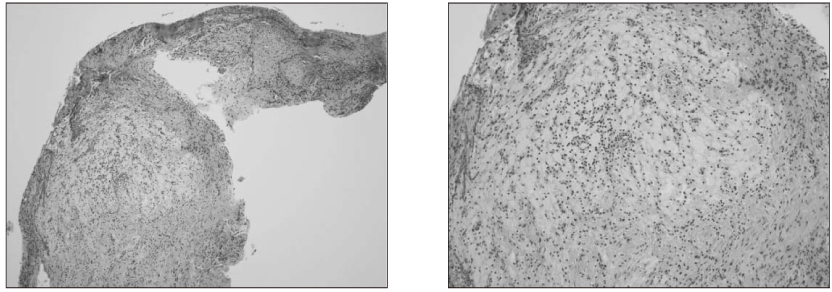

Histological appearance of surgically removed tissue.

jkacd-31-161-g009.jpg

Figure 9 Histological appearance of surgically removed tissue.